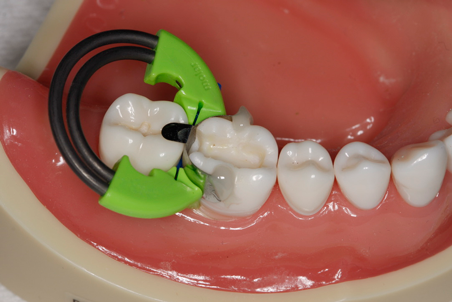

When applying the dual-cured bulk-fill composite, a slight overfill of the cavity prep is important, as stress relief of bonded walls and pulpal floor occurs at the expense of the nonbonded occlusal surface. Auto- and dual-cured composites can be used to mitigate polymer stress in high C-factor restorations and thus prevent pain from pulpal floor gapping postoperatively as well as recurrent caries due to micro-gapping at margins. Dual-cured flowable composites have limited ability to hold a matrix band closely apposed to an adjacent tooth. Consequently, it is critical in developing tight proximal contacts to wedge the teeth prior to preparation of the cavity. This is called prewedging (depicted in Figure 5). Another important consideration is the type of ring, wedge, and matrix employed. The wedge must close off the base of the well-fitting matrix band to prevent overhangs. The separation force of the ring is critical to ensure a good contact with the adjacent tooth. Nate Lawson at UAB found that 28 N was the best measured by Instron, while other researchers claim that 8 pounds measured by removal of ring with forceps is the optimal separation force. Another consideration in selection of the ring and wedge is the amount of separation force generated by these devices. Dr David Clark has discussed that "tack welding" the band to the buccal and lingual of the tooth with flowable composite can be accomplished by holding the band in close opposition to the adjacent tooth with either a matrix adjusting instrument (Bioclear Push-Pull, Bioclear Matrix Systems) or contact-forming instrument (Contact Pro, CEJ Dental) (alternatively: Perform Contact Former, Practicon Dental) (David Clark, DDS, personal communication, December 7, 2022). This does involve using an assistant to light-cure the tack weld; however, it is guaranteed to generate a tight contact (Figure 6 and Figure 7).

Fig 5. Preoperative wedging to create tight

contacts. (Photograph courtesy of Richard

Young, DDS.)

Figure 5